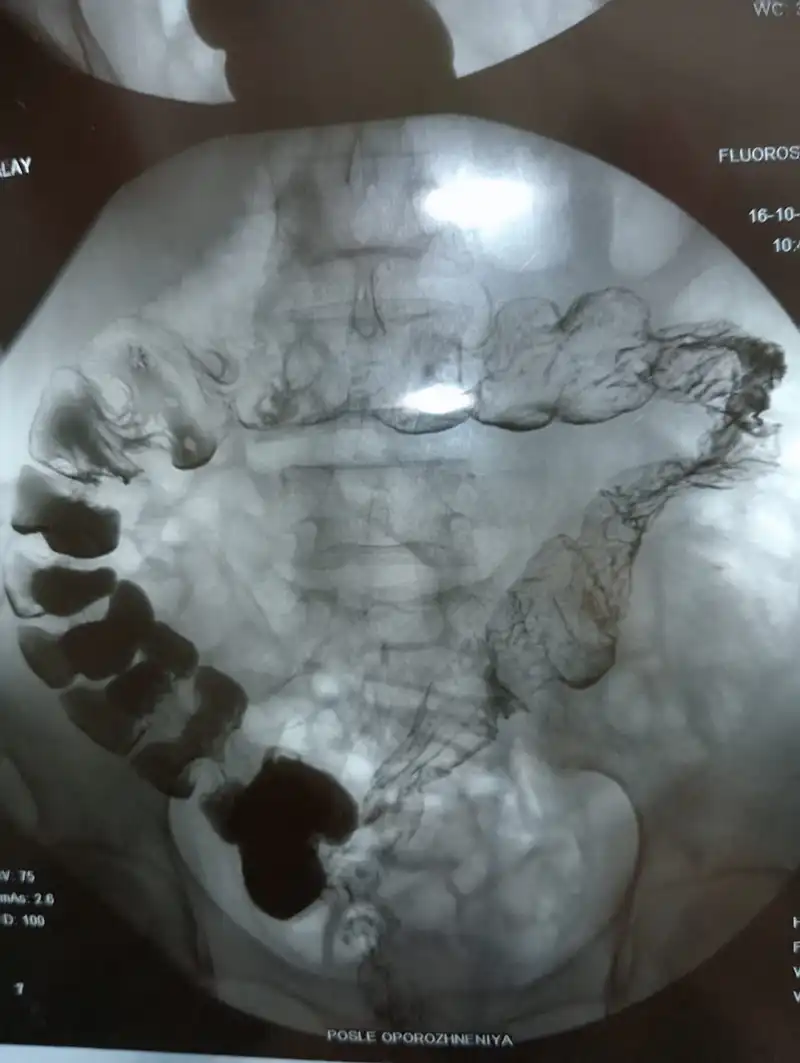

"В итоге я прошла колоноскопию, но ее не удалось провести из-за риска повреждения кишечника. Рентген показал, что мой кишечник был как баллон".

Раздутый кишечник на рентген-снимке. Фото предоставлены Куралай Идрисовой

Кишечник после операции. Фото предоставлено Куралай Идрисовой